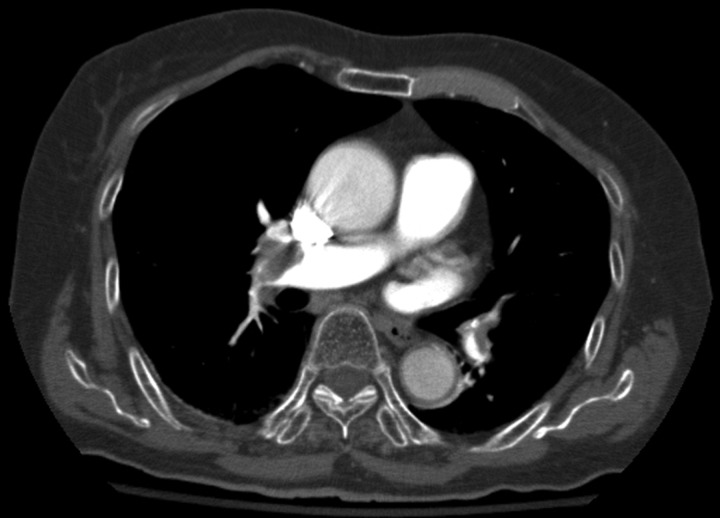

Figure 3.

Thoracic CT (transverse section) showing bilateral pulmonary emboli.

Her abdominal imaging (figures 1 and 2) was negative for any intra-abdominal acute processes and showed significant non-obstructive stool in the colon. It was also remarkable for a wire/catheter fragment in inferior vena cava (IVC) and suspicious findings of PTE in lung fields. A CT scan of her thorax showed a large filling defect in the right main pulmonary artery extending into the lobar and some segmental branches, representing pulmonary embolism. Similar filling defects are seen in the left lower lobe lobar and segmental branches (figures 3 and 4).